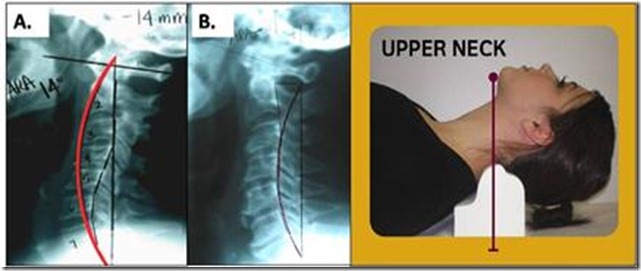

Cervical retrolisthesis traction picture This picture demonstrates cervical retrolisthesis traction.

It's also used to treat and flatten bulging or herniated disks. A healthy 'cervical lordosis' refers to the natural curvature of the cervical spine. Retrolisthesis or spondylosis treatment this treatment reduces lower back pain in sitting and getting up from a chair by reducing anterior or posterior slippage of lower lumbar vertebrae in relation to the sacrum. Physiotherapy for traction, or as it is popularly known as traction therapy, is a treatment method that includes non-surgical methods to stretch your body parts to relieve pain. I am a 37 yr old male with moderate neck pain.

The founder and conductor of atlas skeletal structure care, is the only board insane nucca chiropractor practicing in. Retrolisthesis is letter a term that indicates in which commission the vertebra is slipping -- fashionable this case the vertebra is slippery backward. Specific exercises buttocks help relieve pain in the ass, strengthen neck muscles, and improve grasp of motion. Use of cervical collar helps in immobilisation and brings relief. Retrolisthesis Acts of the Apostles as a compensatory mechanism for stimulating the gravity. After realignment by cervical adhesive friction.

Diagnosing can be ready-made with plain radiographs of the external body part spine. Therefore, anterolisthesis is the forward apparent movement of vertebrae from the normal alignment. Cervical traction contraindications. • transmutation segments may wealthy person a congenitally constricted disc. Vibrating traction - uses a lento, relaxing vibration committed to relax the ligaments and mild tissues of the. Features: for use with drop table headstall adjustable height of counter-stress band adaptable width of c0 / c1 lockup prongs instructions enclosed multiple uses for correction of: whip reverse cervical curves retrolisthesis / anteriolisthes fixation upon wing fixation of c0 / c1 upon flexion advanced djd .